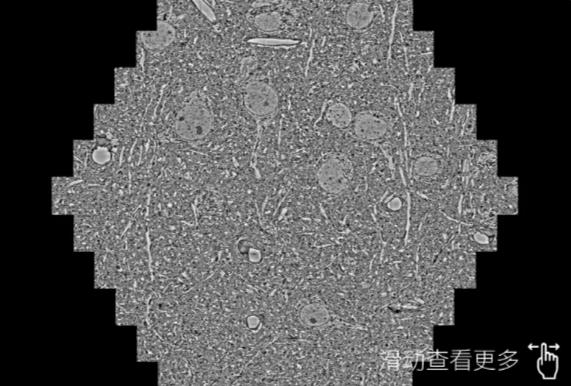

鼠脑切片。左图使用咸宁蔡司咸宁扫描电镜MultiSEM706对165μmx143pm面积区域成像,耗时仅需1.5秒。右图为鼠脑切片中30μm区域放大效果。样品由芝加哥大学B.Kasthuri提供。

使用蔡司高速咸宁扫描电镜MultiSEM对1mm²人脑皮层组织进行高分辨成像,并对其中的各种细胞结构进行三维重构分析。左图展示了2x3mm²组织平面中锥体神经元的三维重构效果。右图显示了局部体积神经元三维重构。图像由哈佛大学chtman实验室提供,渲染图由D. Berger 制作。